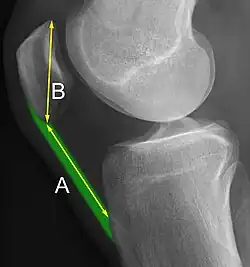

A patella baja is a low-riding patella. A long-standing patella baja may result in extensor dysfunction.[6]

The Insall-Salvati ratio helps to indicate patella baja on lateral X-rays, and is calculated as the patellar tendon length divided by the patellar bone length. An Insall-Salvati ratio of < 0.8 indicates patella baja.[7]